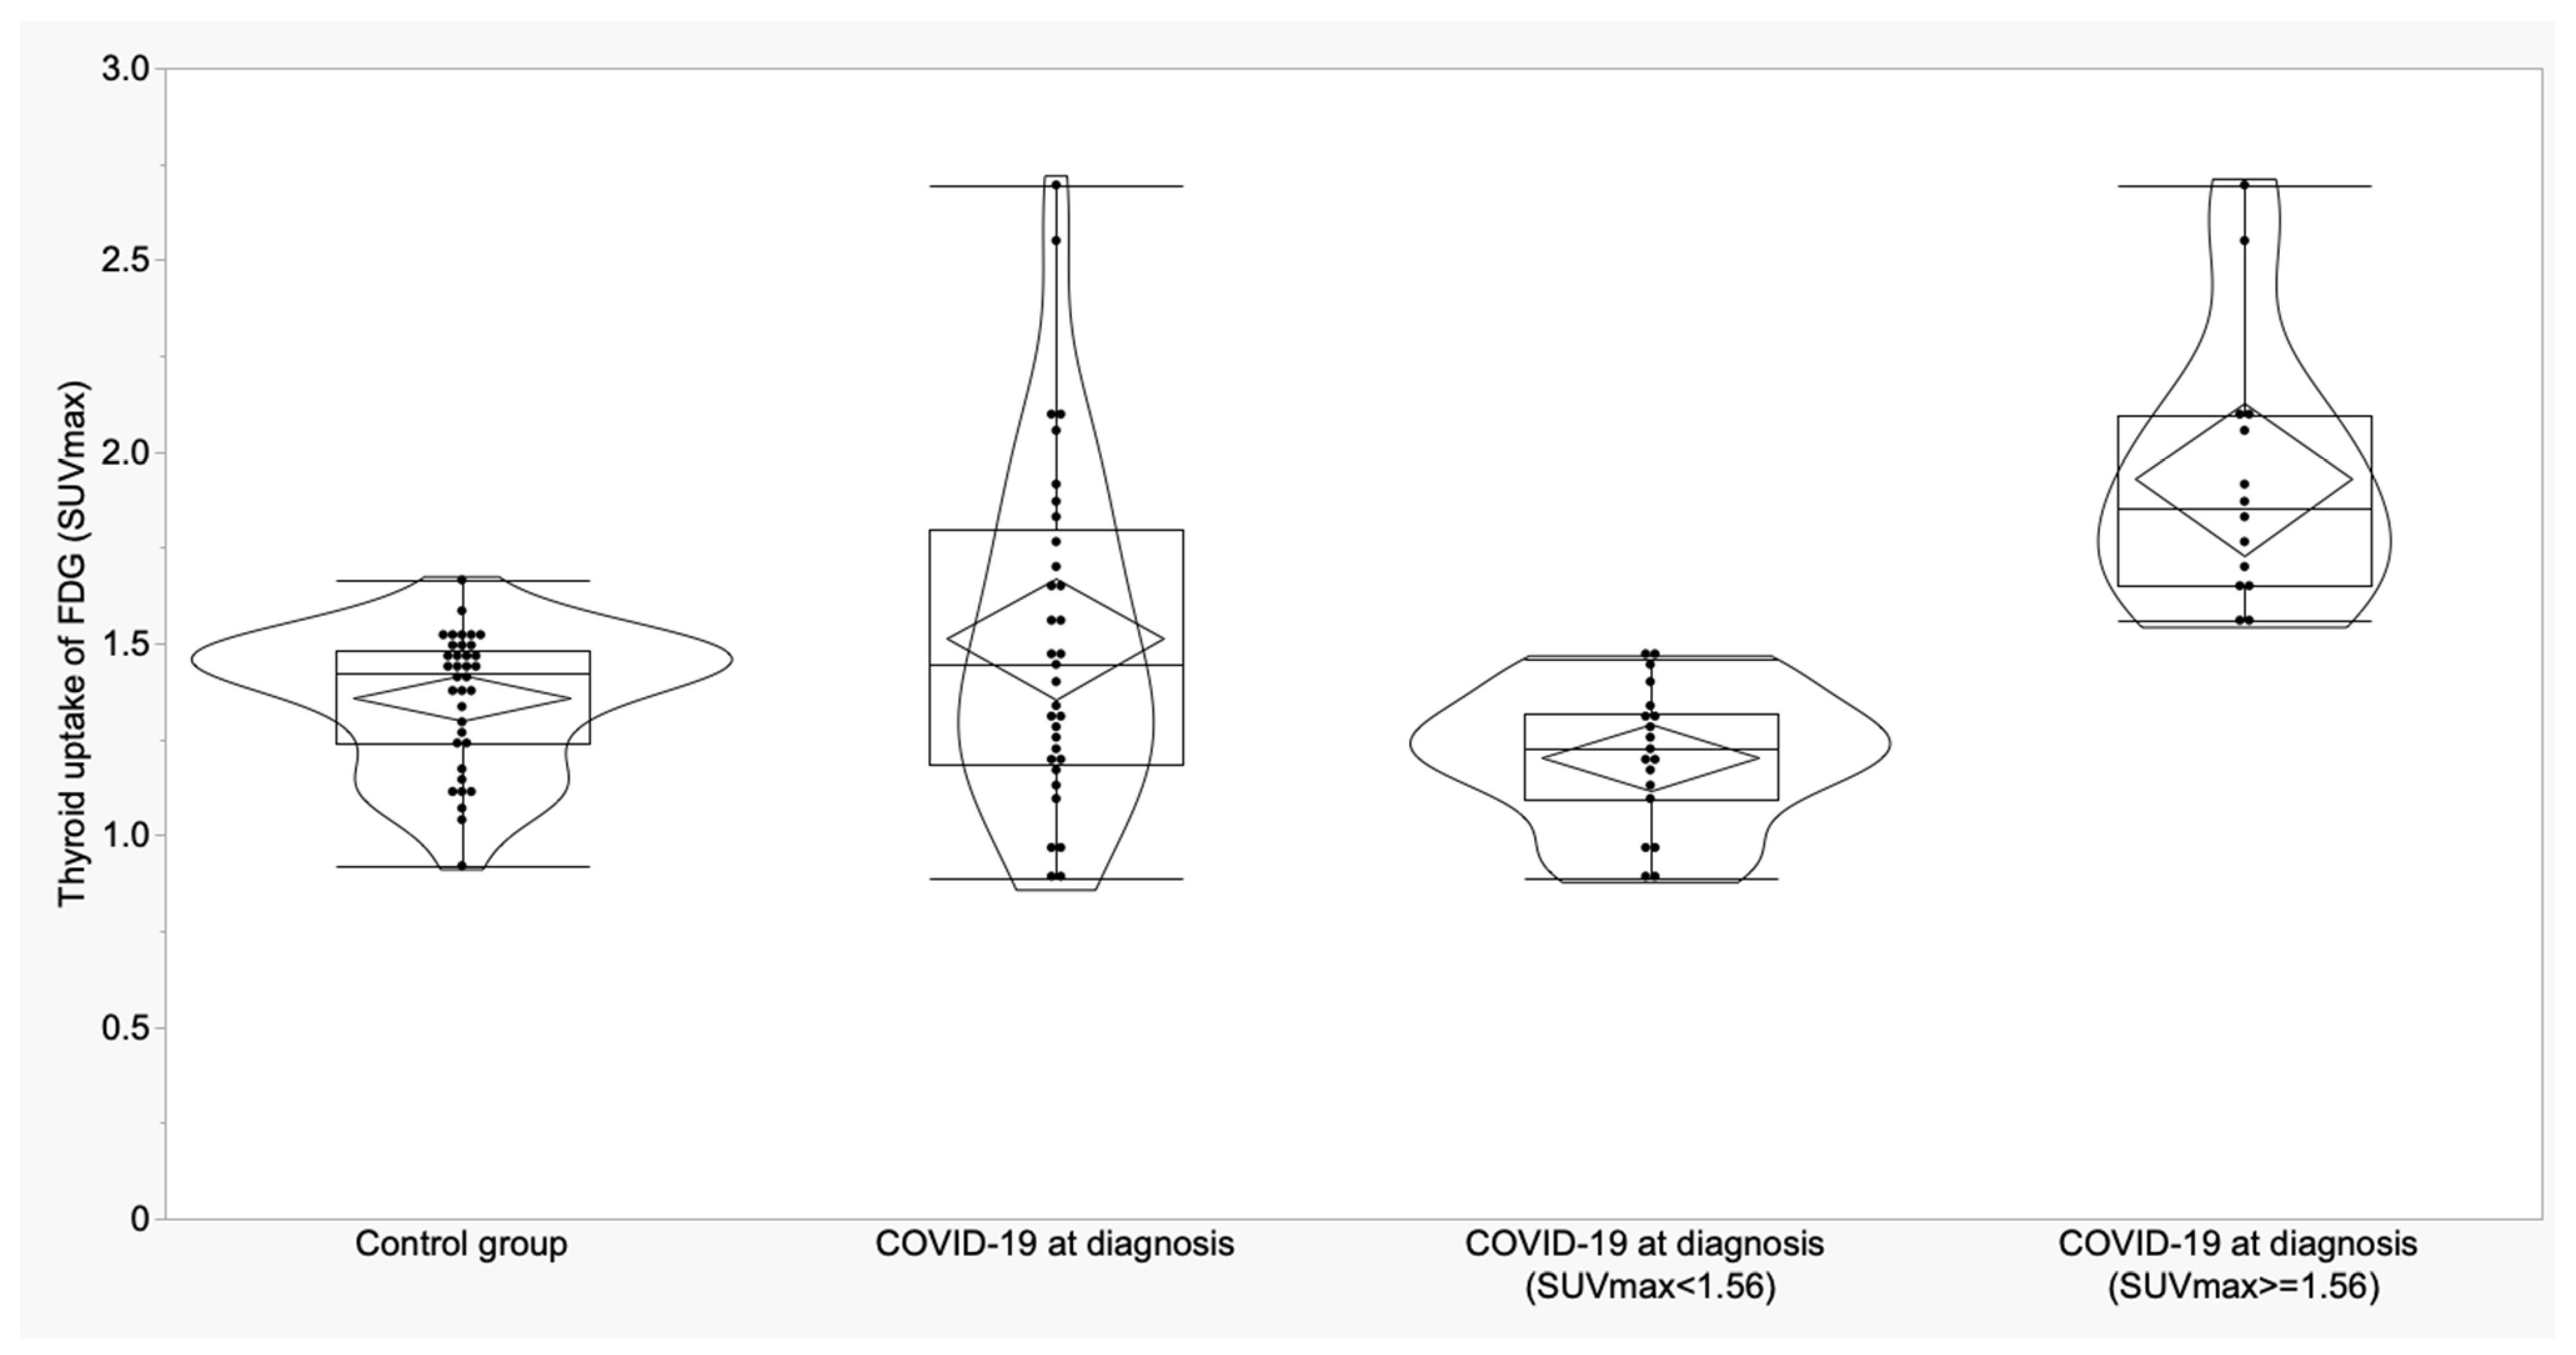

3.2. Thyroid and Adrenal Gland Analysis

| Thyroid (SUVmax) | 1.36 ± 0.18 (1.30 to 1.42) | 1.55 ± 0.47 (1.37 to 1.73) | 1.31 ± 0.24 (1.02 to 1.61) | 0.06 | -- | -- | -- |